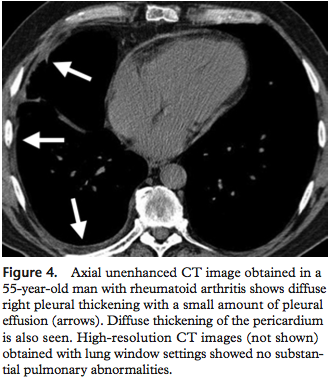

1. Pleural thickening / pleural effusion

rheumatoid arthritis pulmonary manifestation 중 가장 흔한 합병증이 늑막비후로, rheumatoid arthritis환자의 약 39-73%에서 보인다. 단, 늑막삼출은 드물어서 5%에서만 보인다.